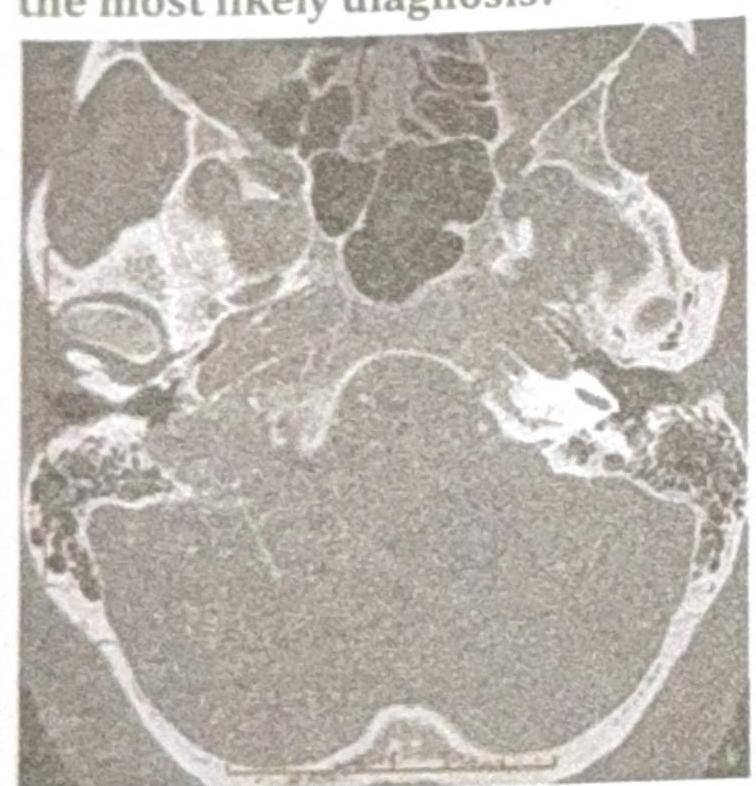

A patient presents with conductive hearing loss, pulsatile tinnitus, and a positive Phelps sign. Based on the CT scan image provided, what is the most likely diagnosis?

Explanation: ***Glomus Jugulare*** - The symptoms of **conductive hearing loss**, **pulsatile tinnitus**, and a **positive Phelps sign** (destruction of the bone separating the carotid artery from the jugular bulb on CT) are classic for a glomus jugulare tumor. - The CT scan image, showing a destructive lesion in the **jugular foramen** region, further supports this diagnosis, as these tumors originate from the paraganglia of the jugular bulb. *Glomus Tympanicum* - While it can cause conductive hearing loss and pulsatile tinnitus, a glomus tympanicum tumor is typically **confined to the middle ear cavity** and does not involve bone erosion of the jugular foramen as indicated by a positive Phelps sign. - The CT findings would show a mass in the middle ear, often behind an intact tympanic membrane, rather than extensive bone destruction in the jugular region. *Acoustic Neuroma* - This tumor, also known as a **vestibular schwannoma**, primarily causes **sensorineural hearing loss**, **tinnitus** (often non-pulsatile), and **balance issues**, not conductive hearing loss or pulsatile tinnitus. - An acoustic neuroma is located in the **cerebellopontine angle** and internal auditory canal, and the CT scan would show a mass in this specific location, not necessarily bone erosion of the jugular foramen. *Cholesteatoma* - A cholesteatoma is a **destructive, expanding growth of keratinizing squamous epithelium** in the middle ear or mastoid, typically presenting with **conductive hearing loss**, **otorrhea**, and sometimes headaches. - It does not typically cause pulsatile tinnitus unless it's very large and vascularized, nor does it present with the characteristic destruction of the jugular foramen seen with a positive Phelps sign.

A patient presents with conductive hearing loss, pulsatile tinnitus and a positive Phelps sign. Using the CT scan provided, identify the condition.

Explanation: ***Glomus jugulare*** - This diagnosis aligns with the presence of **conductive hearing loss**, **pulsatile tinnitus**, and a **positive Phelps sign**, which indicate a highly vascular tumor in the jugular foramen. - While exact details of the CT scan are difficult to discern from the provided image, the clinical context strongly points towards a **glomus jugulare tumor**, known for its characteristic bone erosion around the jugular bulb seen on imaging. *Glomus tympanicum* - This typically presents with **pulsatile tinnitus** and **conductive hearing loss**, but is usually observed as a red mass behind an intact tympanic membrane, arising from the **promontory** within the middle ear space. - It would not typically cause a **Phelps sign**, which specifically relates to erosion of the jugular foramen region. *Acoustic neuroma* - An acoustic neuroma (vestibular schwannoma) causes **sensorineural hearing loss**, often unilateral, not conductive, along with **tinnitus** (usually non-pulsatile) and **balance issues**. - It arises from the vestibular nerve within the **internal auditory canal** and cerebellopontine angle, and does not cause a Phelps sign. *Otosclerosis* - Otosclerosis is characterized by **conductive hearing loss** due to abnormal bone growth fixing the stapes in the oval window, but it does not cause **pulsatile tinnitus** or involve a **positive Phelps sign**. - The disease involves the **otic capsule** and typically does not present with a tumorous mass visible on CT in the jugular foramen area.